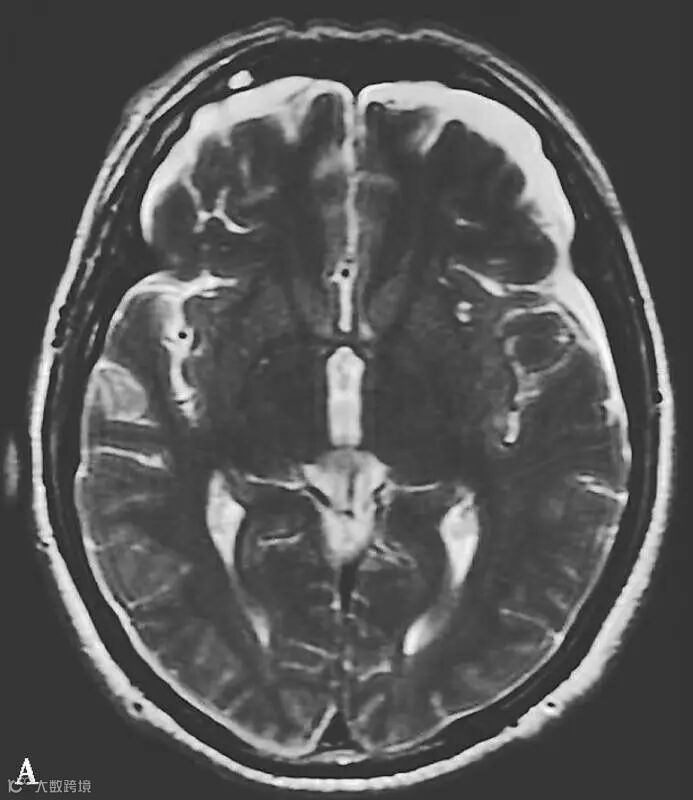

图6-11-1 弥漫性轴索损伤并双侧额部硬膜下积液、双侧顶枕部硬膜下血肿

男,34岁,外伤后7天。A~H(A、B.T2WI,C、D.T1WI,E、F.T2WI-FLAIR,G、H.DWI):左侧岛叶及右侧顶叶白质可见斑片状稍长T1稍长T2信号,边缘不清,FLAIR及DWI呈高信号。双侧额部内板下可见新月形长T1长T2信号,FLAIR及DWI呈低信号。双侧顶枕部内板下可见弧形短T1长T2信号,FLAIR及DWI呈高信号